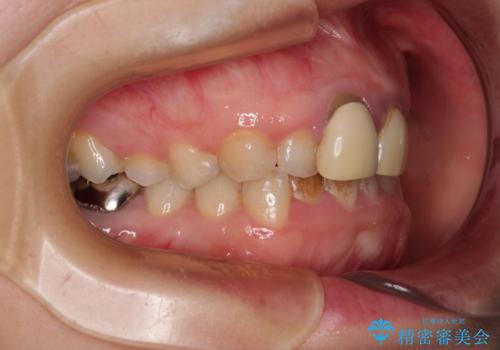

- 前歯のデコボコと、着色が著しい保険診療の前歯クラウンを気にして来院された患者様です。

左上の犬歯が埋伏しており、CT画像より萌出は困難と判断されたため、残存している歯にて歯列と咬合を整えることとしました。

マウスピース装着は煩わしいとのことで、表側のワイヤー装置にて矯正治療を行うこととしました。